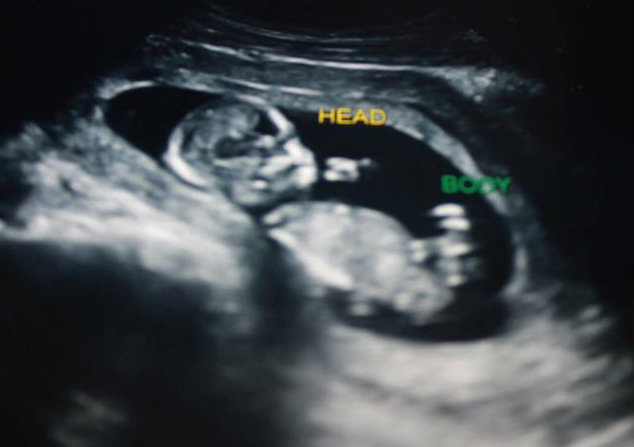

13 week ultrasound - can you see a nub? Lovemy4, please help! :)

I had an ultrasound yesterday at 12 weeks 5 days. Baby was measuring 13 weeks 3 days. Heart rate was 167. Baby was moving around a lot and I'm not sure if I ever saw a clear nub at all. :( I did see a potty shot and didn't see anything protruding between the legs at all, I saw what looked like a white spot between the legs (didn't see three lines, but wondering if it may have been girly parts seen from a distance, it wasn't a very close-up shot). My symptoms this pregnancy have been identical to my previous girl pregnancy. I don't have a gender preference, but this just feels like a girl to me. Any thoughts? If the nub isn't visible, what do you think based on skull shape? I thought the profile reminded me of my daughter, she had a rounded forehead like this, and my son's was very straight.